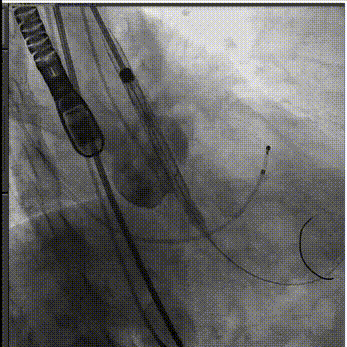

手术过程:

主动脉根部造影

人工瓣膜精准定位

释放工作位评估

术后造影评估

超声显示假体瓣膜形态良好,工作正常,微量瓣周漏。